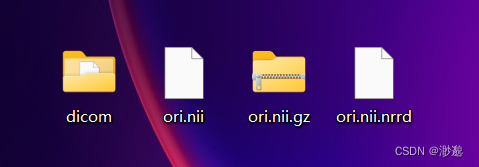

运行代码可以发现dicom文件已经成功被转换为了三种格式。

事实上,我们希望更多使用nii.gz格式